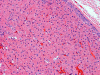

Pathology of the Case: Grossly, the tumor was a small 1 x 2 cm well demarcated nodule embedded within the mid portion of the salivary gland. There is no true capsule (Panel A). The tumor cells arrange in solid sheets and without specific pattern formation (Panel B and C). There is no collagenous tissue within the tumor. The tumor cells are polygonal and rather homogeneous in size. They have low-grade, centrally located nuclei (Panel D), finely granular and distinctly eosinophilic cytoplasm. The granular feature is best appreciated in the cytoplasmic preparation that is prepared while the tumor is being examined before fixation (Panel E). There is no necrosis or mitotic figures.

Microscopically, oncocytes have a very characteristic appearance with granular eosinophilic cytoplasm due to marked increase in the number of mitochondria mitochondria, pleomorphism of mitochondria, and a paucity of other organelles. The tumor cells have little variation among different tumors or different part of the same tumor. Characteristically, the tumor cells are rather uniform and polygonal in shape. The cytoplasmic membrane can be readily recognized. The nuclei are usually round, centrally located, and nucleoli are present. The cells are arranged in uniform solid sheets without a specific pattern or they may aggregate into clusters, and sometimes they form duct-like structures. Thin fibrovascular septa are present. Oncocytomas may have a clear cell component secondary to accumulation of cytoplasmic glycogen 6. A PAS stain with and without diastase digestion will be very helpful in recognizing the glycogen. High grade nuclear atypia is only seen exceptionally. Phosphotungstic acid hematoxylin (PTAH) is a good stain that would stain the mitochondria dark. However, the stain is rarely called to service for this purpose as the cytoplasm is typically characteristic enough for recognition without special stain. In clear cell variants, however, PTAH may help. Mitotic figures are not readily seen. In most situations, the diagnosis of oncocytoma is not a particularly challenging one.